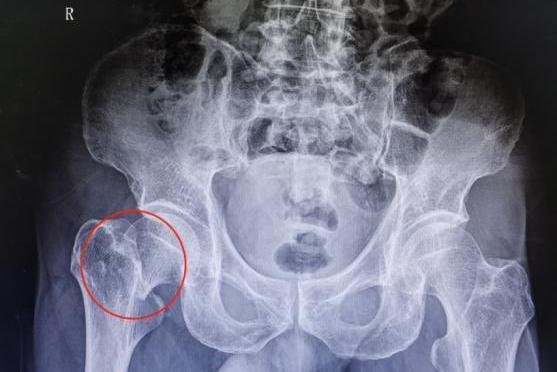

髋关节骨折手术后能够下地行走的时间因人而异,取决于多种因素,比如身体情况、骨折类型、年龄等,短的可能需要3-5天,当长的可能需要2-8周,甚至更久的时间。

- 如果骨折情况复杂,如粉碎性骨折,或者患者本身存在基础疾病,如糖尿病、心血管疾病等,影响了身体的恢复能力,下地时间可能会推迟,如延后到术后2-3周甚至更久。比如严重的髋臼骨折,术后可能需要3周左右才能考虑下地。